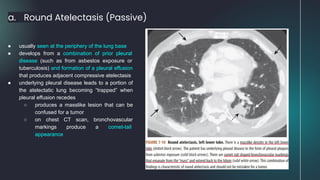

a. Round Atelectasis (Passive)

● usually seen at the periphery of the lung base

● develops from a combination of prior pleural

disease (such as from asbestos exposure or

tuberculosis) and formation of a pleural effusion

that produces adjacent compressive atelectasis

● underlying pleural disease leads to a portion of

the atelectatic lung becoming “trapped” when

pleural effusion recedes

○ produces a masslike lesion that can be

confused for a tumor

○ on chest CT scan, bronchovascular

markings produce a comet-tail

appearance